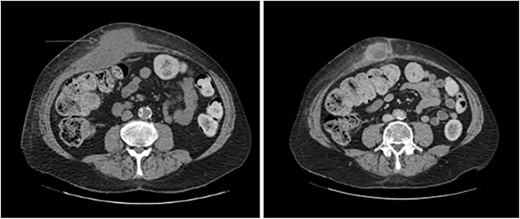

A 65-year-old gentleman with a body mass index of 29.6 and medical history of Guillain–Barré syndrome, type 2 diabetes mellitus, hypertension, and chronic pain was referred to our outpatient clinic with intermittent upper abdominal pain. His surgical history included an open appendicectomy. He was wheelchair-bound outside his home and received weekly assistance from a carer. On examination he was anicteric. His abdomen was soft, but a mildly tender mass was palpable in the right upper quadrant. An initial computed tomography (CT) scan showed thickening of the gallbladder and a collection extending from the fundus and infiltrating the anterior abdominal wall (Fig. 1). Further scans showed extension of the collection towards the midline (Fig. 2). He subsequently presented to the emergency department with purulent discharge from an external orifice adjacent to the umbilicus. An ultrasound-guided 6Fr pigtail drain was then placed into the known abdominal wall collection.

CT abdomen with portal venous contrast in axial plane showing extension of collection towards the paraumbilical region.